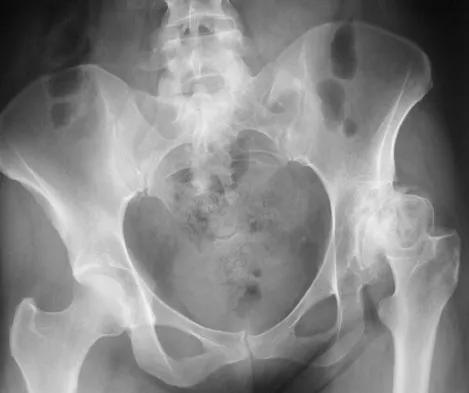

A 21-year-old collegiate female cross-country athlete reports right hip pain that begins about 12 miles into a run, followed by pain resolution when she discontinues running. However, each time she tries to resume a running program, she experiences recurrence of pain deep in the anterior groin. A plain radiograph and MRI scan are shown in Figures 8a and 8b. Management should consist of

Explanation

The history is consistent with a stress fracture. Findings on the plain radiograph are marginal, but the MRI scan shows evidence of stress reaction in the medial neck of the femur (compression side). A lesion on the compression side is not normally at risk for displacement and usually can be managed nonsurgically. A bone scan would further identify the lesion but is not necessary. A skeletal survey and chest radiograph are used in staging a tumor. Radioisotope injection and guided biopsy are sometimes used for osteoid osteomas. Boden BP, Osbahr DC: High-risk stress fractures: Evaluation and treatment. J Am Acad Orthop Surg 2000;8:344-353.